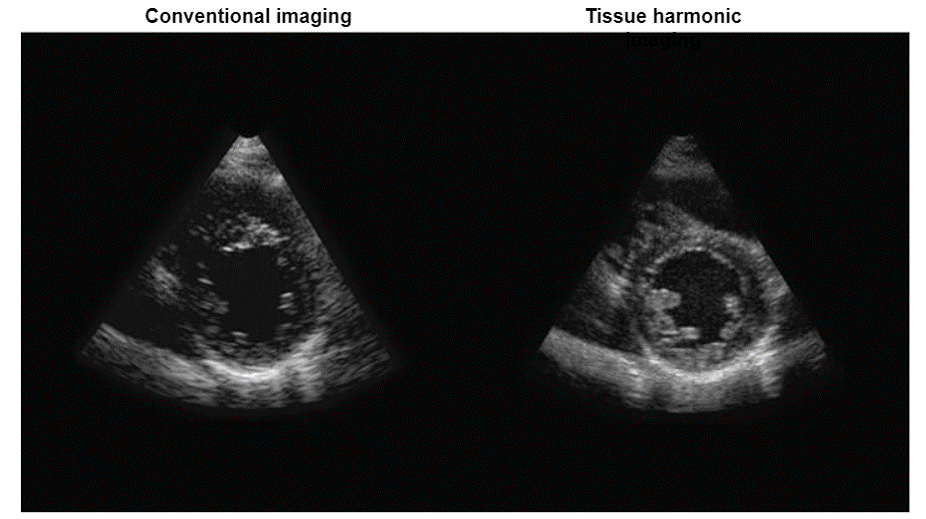

As we mentioned previously, the transmitted pulse consists of a range of frequencies centered around f0. In a linear medium, the echo pulse frequency is the same as the fundamental frequency but has lower energy, whereas the nonlinear medium results in harmonic waves of higher frequency and lower energy as shown in this figure. It is important to note that the majority of clinical US systems use second harmonic (ie, 2f0) echoes for THI image formation.

Clinical Advantages

The advantages of harmonic imaging include, but are not limited to improved signal-to-noise ratio and reduced artifacts, or better axial and lateral resolutions due to higher frequencies and narrower beams.